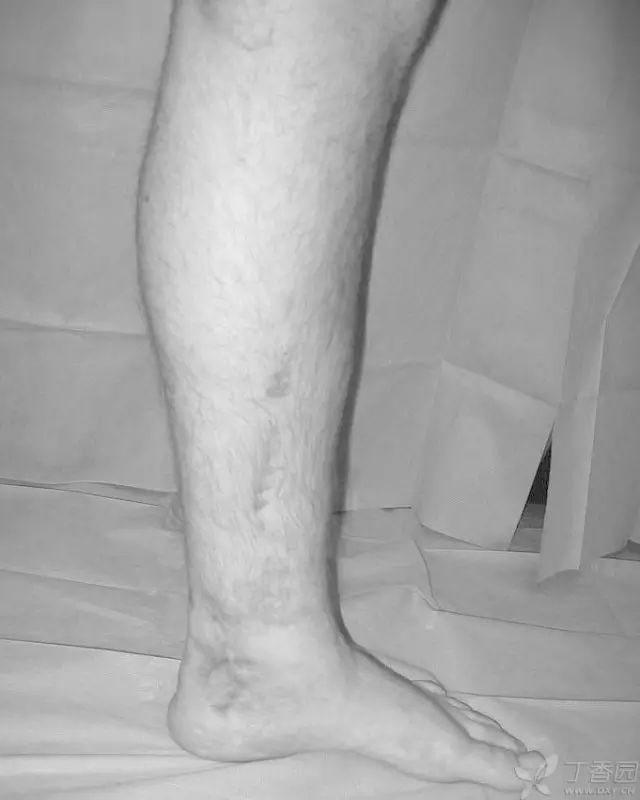

33 岁男性,车祸多发伤。左踝严重污染,几乎环形创口,胫骨远端 20 cm 缺损

游离骨块生理盐水灌洗,保持湿润,4 小时内紧急手术。术中对创口和游离骨块各用 12L 生理盐水灌洗,彻底清创。外固定支架固定,创口松散地缝合

原计划 48 小时再次灌洗,因身体情况不稳定,10 天后再次进手术室清创灌洗,方法如前;48 小时后进行了第三次灌洗,然后进行了内固定,闭合创口。

3 个月后创口无感染迹象,骨折处无压痛

6 个月后,骨折线模糊,独立行走

18 个月恢复工作